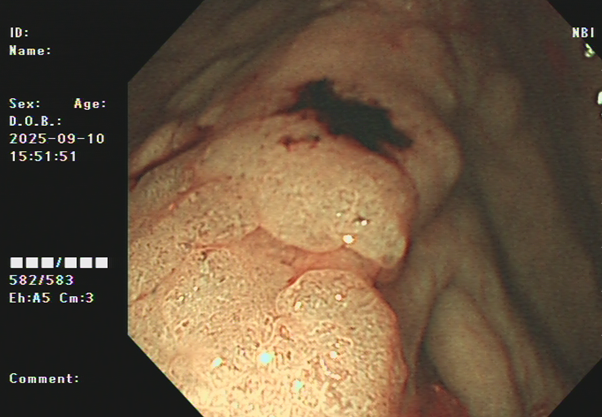

吴姨(化名)平素饮食规则,无腹痛、便血等消化道不适,因其侄女有大肠肿瘤病史,为求安心,特从外地来连州市人民医院进行肠镜检查。消化内镜室吕美光医生在检查中,凭借丰富经验和高清放大染色内镜技术,于盲肠深处发现一个与正常黏膜极其相似、范围达35mmX45mm的平坦微隆起型病灶,并确认其微表面及微血管结构存在异型。后续活检证实,该病灶为盲肠管状腺瘤。

潘新智主任介绍,盲肠侧向发育型肿瘤(LST)是一种发生在盲肠部位的特殊类型的肿瘤,这种肿瘤通常呈扁平状增生,紧贴肠壁,像烙饼一样,具有比普通息肉更高的恶变潜能。由于其特殊的生长方式,盲肠侧向发育型肿瘤在内镜下治疗相对困难,耗时较长,肠道穿孔出血的风险较高,需要医生具备敏锐的观察力和丰富的经验。